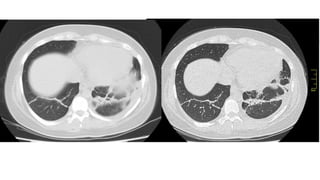

Hallazgos atípicos en TC de TX - Complicaciones

●Linfadenopatía mediastínica

●Derrame pleural

●Nodulillos centrolobulillares

●Patrón de árbol en brote

●Engrosamiento de la pared bronquial

●Cavitación

●Neumotórax

Neumomediastíno

Neumotórax

TEP